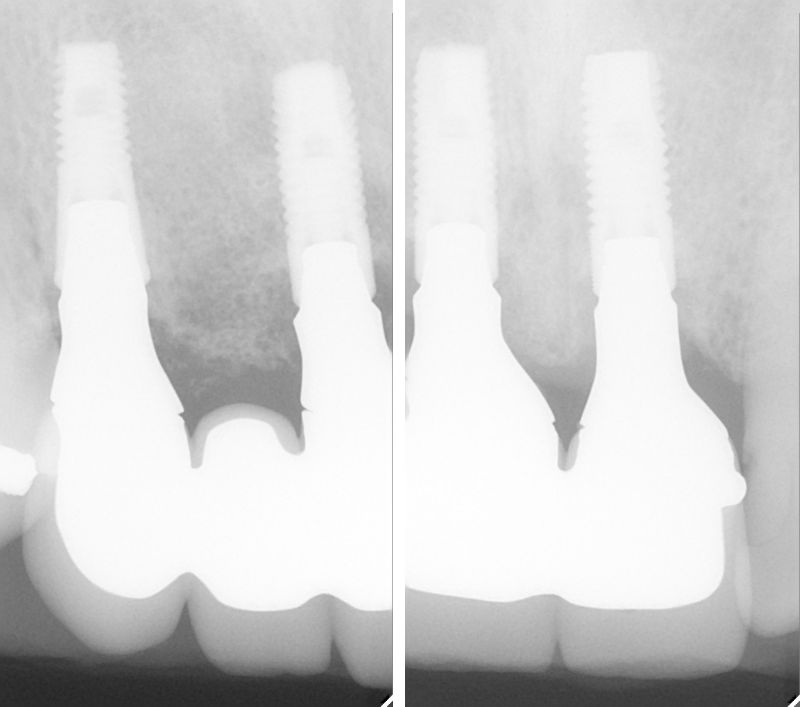

インプラント治療の症例紹介⑧

Before

After

歯の欠損部の後方に既にインプラントが埋入されていたケース。欠損部にインプラントを埋入し上部構造で連結しました。

既存のインプラントと追加埋入を行ったインプラントを連結し完成させた症例です。